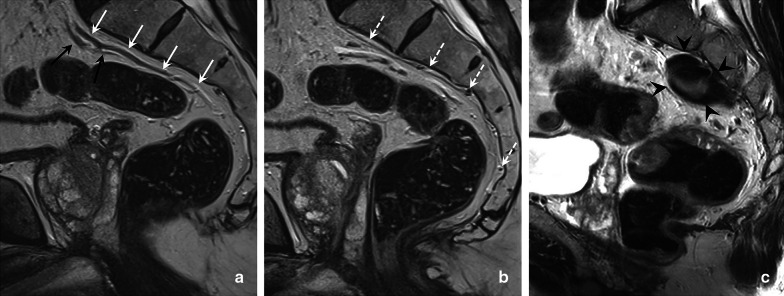

Various definitions and landmarks have been used throughout the years to determine the upper boundary of the rectum, including the sacral promontory, third sacral vertebra, anterior peritoneal reflection, and distance measurements from the anorectal junction or anal verge [4, 17, 18]. The main clinical significance of defining the upper limit of the rectum during tumour staging is to differentiate rectal tumours from tumours arising in the sigmoid colon. Patients with sigmoid cancers are primarily managed with upfront surgery, while patients with rectal cancers usually undergo differentiated treatments varying from surgery only in low-risk tumours to short or long course neoadjuvant (chemo)radiotherapy in intermediate and high-risk tumours [4, 14, 15]. Recently, an international multidisciplinary expert consensus panel agreed on the “sigmoid take-off” (STO) as the preferred landmark to define the boundary between the rectum and sigmoid colon on imaging [19]. The STO marks the junction between the mesorectum and sigmoid mesocolon and can be recognised on sagittal views as the point from which the sigmoid sweeps horizontally (away from the sacrum) and on axial views as the point from which the sigmoid projects ventrally (Fig. 3).

Fig. 3.

Sagittal and axial T2-weighted images of a normal rectum of a male individual (without rectal cancer) demonstrating the sigmoid take-off (STO, indicated by the *) as the point from which the sigmoid sweeps horizontally on a sagittal view (a) and ventrally on an axial view (b), away from the sacrum. The white dashed line on the sagittal view indicates the anorectal junction (ARJ) that is typically situated at the level of an imaginary line between the lower margin of the sacral and pubic bone

Recognising the STO on imaging requires some training. It may be challenging due to variations in the anatomical course of the rectosigmoid related to the degree of luminal distension (by tumour or gas), mass effect from adjacent organs, pelvic floor insufficiency, or surgical history. The inconsistent angulation of axial imaging planes on MRI may also be a challenging factor [20, 21]. Nevertheless, the STO is generally considered an intuitive landmark. In 2019, the Dutch guidelines on colorectal cancer were one of the first to adopt the STO as a formal landmark to discern rectal from sigmoid cancer, defining rectal cancer as any tumour with a lower boundary starting below the level of the STO and sigmoid cancer as any tumour situated entirely above the level of the STO [14]. Reports from the Netherlands have shown that this new definition can impact treatment planning (e.g. the choice of surgery or neoadjuvant treatment) compared to traditional approaches with no standardised definitions in up to 19% of patients with tumours near the rectosigmoid junction [20].